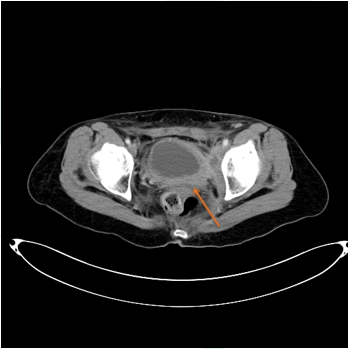

盆腔内膀胱后方有不规则软组织影

膀胱壁不均匀增厚

影像报告